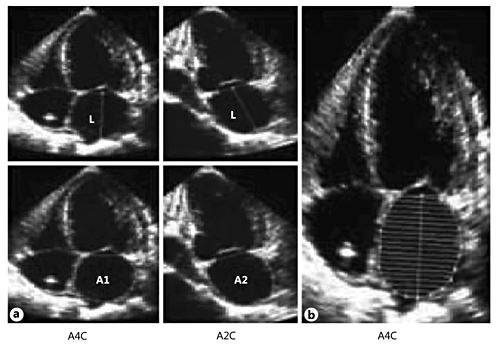

The anteroposterior diameter (calculated by M-mode or 2D echocardiography), although the most widely used measurement of LA size in clinical practice, is no longer considered an adequate representation of the true LA dimension because it relies on several geometric assumptions and often results in an underestimation of LA size. On the other hand, echocardiographic measurements of LA volume using 2D echocardiography or RT3DE rely on fewer geometric assumptions than the anteroposterior diameter [39] and have been validated against cine-computed tomography, contrast ventriculography and MRI [37, 40, 41]. Thus, it is recommended that LA volume measurements be based either on an ellipsoid model or the Simpson's method in 4-chamber and 2-chamber apical views (fig. 4), even though LA border visualization is suboptimal in some cases. The size of the LA varies during the cardiac cycle, but only the maximum LA size and volume are routinely measured. Table 1 shows how to avoid pitfalls in order to accurately measure LA volumes during daily clinical practice [42].

LA volume calculation using 2D echocardiography. a Biplane area-length method using the formula V = 8(A1)(A2)/ 3π(L), where V is volume, A1 and A2 represent the LA planimetry in the apical 4-chamber (A4C) and 2-chamber (A2C) views, respectively, and L is the shortest length from the middle of the plane of the mitral annulus to the superior aspect of the LA. b Modified single-plane Simpson's rule, assuming the stacked disks are circular, using the formula V = π/4(h)Σ(D), where V is volume, h is the height of the disks and D is the orthogonal axis of the disks.